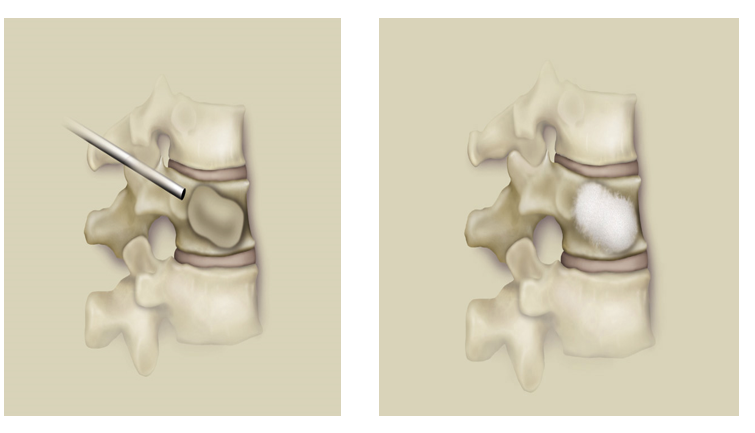

经皮椎体成形术及经皮椎体后凸成形术都属于治疗疼痛性椎体压缩性骨折的微创技术,与 PVP 不同的是,PKP 在注入骨水泥之前首先利用可扩张性球囊或其他装置置入椎体内并膨胀,从而尽量恢复椎体的高度并降低推注骨水泥的压力。

两者都是通过经皮穿刺的方法向椎体内注入骨水泥材料,以达到消除骨折微动、增强椎体的力学强度与缓解腰背疼痛的目的。

与 PVP 不同的是,PKP 在注入骨水泥之前首先利用可扩张性球囊或其他装置置入椎体内并膨胀,从而尽量恢复椎体的高度并降低推注骨水泥的压力。

此法在椎体成形基础上,先用特制的气囊将压缩椎体复位,然后在低压下注入骨水泥,减少渗漏

放入可扩张球囊,确保球囊位于椎体内(扩张前透视)扩张球囊:先加入2ml左右造影剂,同时时观察压力表,后每次增加造影剂0.5ml,透视至椎体扩张到满意程度,球囊系统压力控制在15个大气压左右。

注入骨水泥

• 骨水泥呈牙膏状开始注入

• 填充量:胸椎2-4ml,腰椎4-6ml